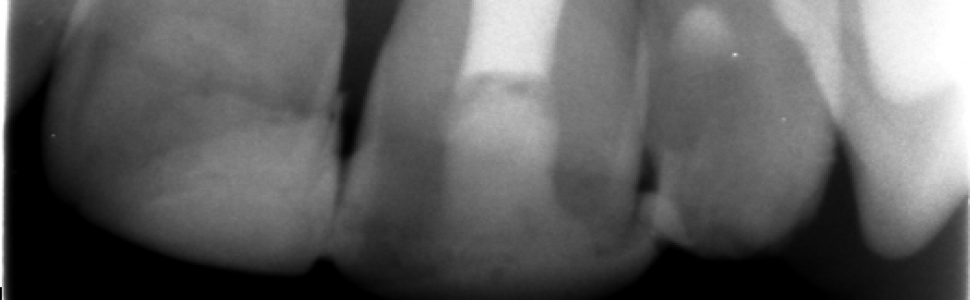

W opisywanym przypadku u pacjenta stwierdzono całkowite zwichnięcie zęba 21 (kl. V wg Ellisa). Suchy ząb przez około 2 godziny był przechowywany w chusteczce. Ostatecznie umieszczono go w zębodole i zszynowano włóknem szklanym do zębów 11 i 22. Proces regeneracji po urazie wspomagano zabiegami fizykalnymi: laseroterapią i magnetostymulacją. Kilkunastomiesięczna obserwacja, wspomagana wykonaniem zdjęć rentgenowskich, nie wykazała zmian w przyzębiu wierzchołkowym i brzeżnym.

Teeth from Ellis Class V (the extraction tooth sometimes described as the completely avulsed tooth) are replantation. A case report: Patient with V by Ellis – the completely avulsed tooth 21. Tooth about 2 hours was dry in a handkerchief. The tooth was replanted and immobilized using a composite splint with teeth 11 and 22. Use was made of additional physical therapy: laser and low magnetic fields. After a few months of preliminary observation (radiodiagnostics) a satisfactory result of the treatment was obtained.